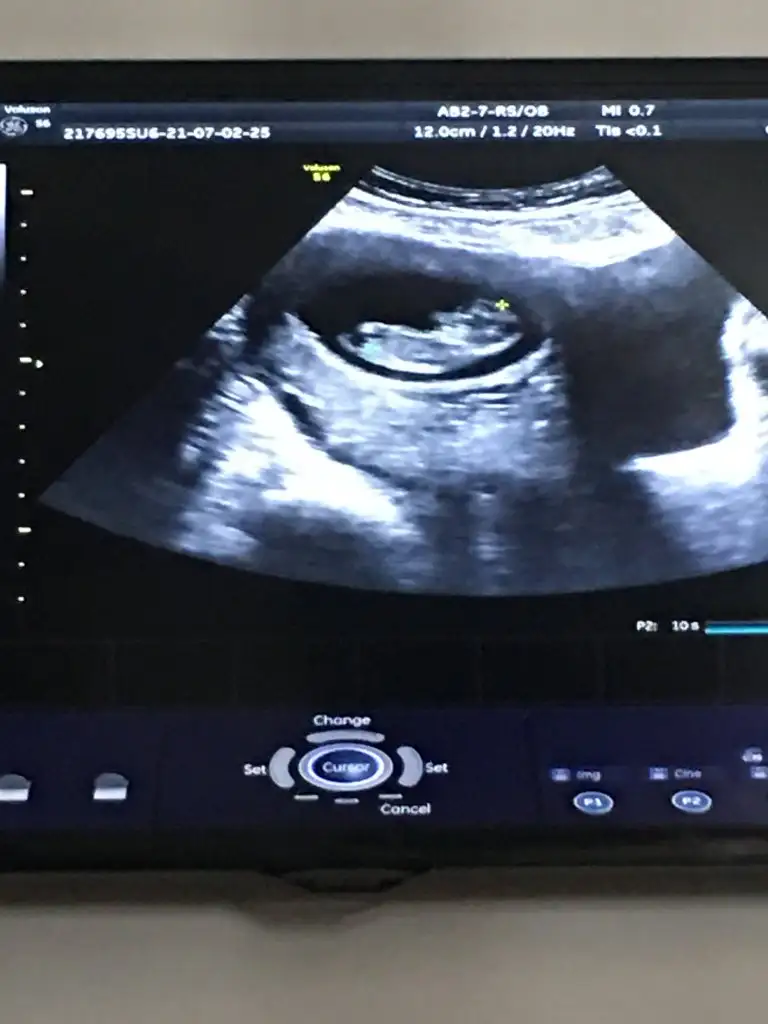

@tülperde merhaba aranıza yeni katıldım 10+2 görüntüm var bugun rica etsem yorumlarmısın

Bugün 10+2 yim kanama alanlarım var ama çok küçükmüş doktor birşey olacağını sanmıyorum dedi progestan hapa devam ediyorum bu görüntüde hala bebeğimi ayırt edemiyorum başı hangi tarafta ayakları nerde görebilen var mı